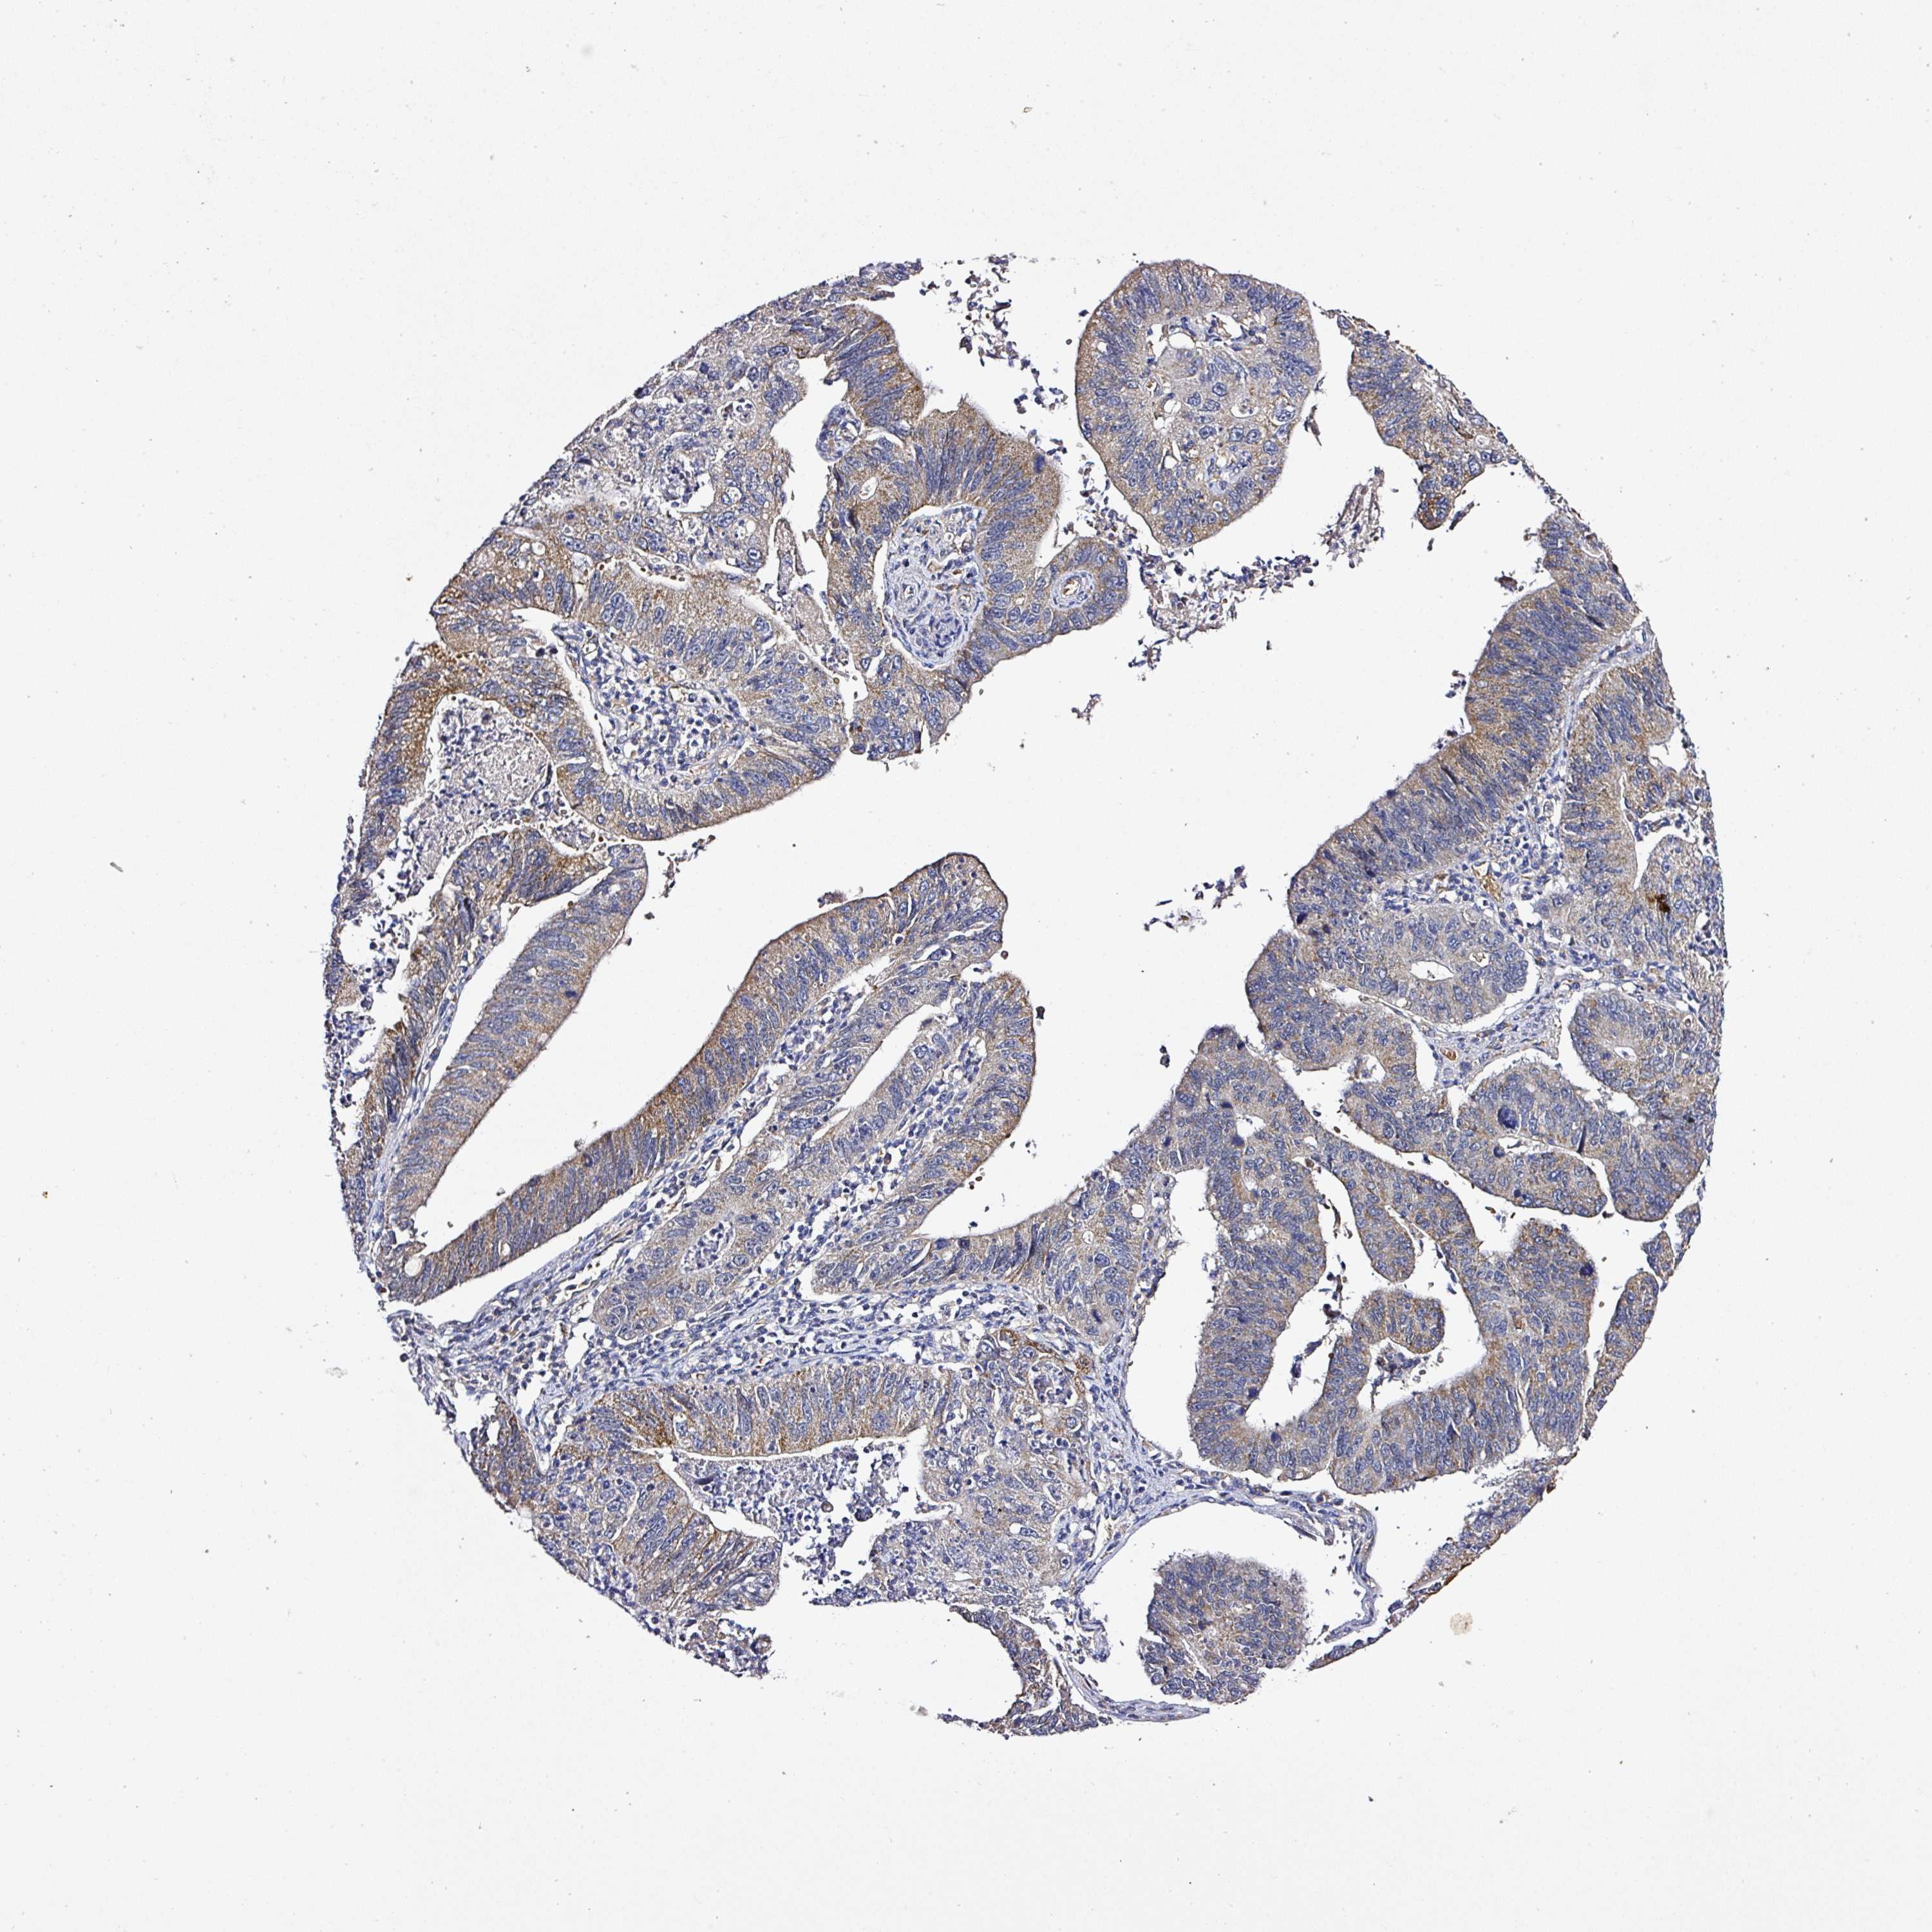

STOMACH CANCER - Protein expressioni

A mouse-over function shows sample information and annotation data. Click on an image to view it in a full screen mode. Samples can be filtered based on level of antibody staining by selecting one or several of the following categories: high, medium, low and not detected. The assay and annotation is described here.

Note that samples used for immunohistochemistry by the Human Protein Atlas do not correspond to samples in the TCGA dataset.

Antibody stainingi

Antibody staining in the annotated cell types in the current human tissue is reported as not detected, low, medium, or high, based on conventional immunohistochemistry profiling in selected tissues. This score is based on the combination of the staining intensity and fraction of stained cells.

Each image is clickable and will lead to virtual microscopy that enables deeper exploration of all samples and also displays staining intensity scores, fraction scores and subcellular localization as well as patient and tissue information for each sample.

Antibody HPA051493

Staining

High

Medium

Low

Not detected

Intensity

Strong

Moderate

Weak

Negative

Quantity

>75%

75%-25%

<25%

None

Location

Nuclear

Cytoplasmic/membranous

Cytoplasmic/membranous,nuclear

Adenocarcinoma, NOS